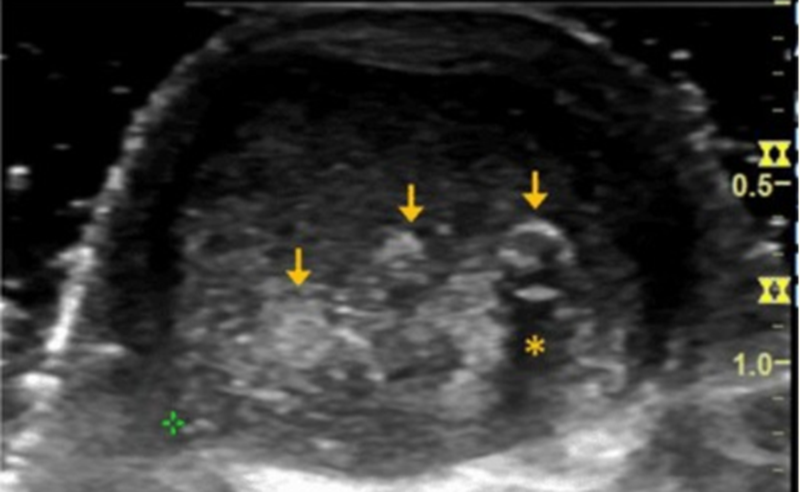

CT扫描显示右侧与L4-L5关节突关节相关的钙化滑膜囊肿,明显侵犯椎管

A、注射钆前轴位T1加权MRI扫描显示硬膜囊背侧有低信号钙化肿块移位;B、注射钆后,低信号区周围可见强化环;C、矢状位T2加权MRI图像。箭头显示侧隐窝内有囊性肿块